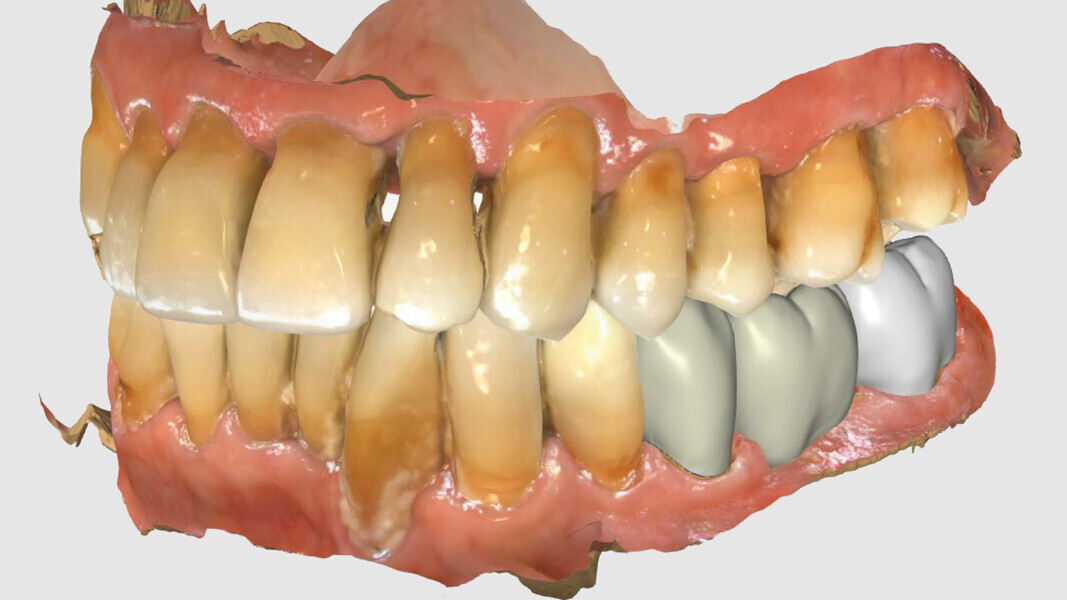

Fig. 2: Clinical situation at the initial appointment in the dental practice.

Fig. 3: Open bite in the mandibular left posterior region.